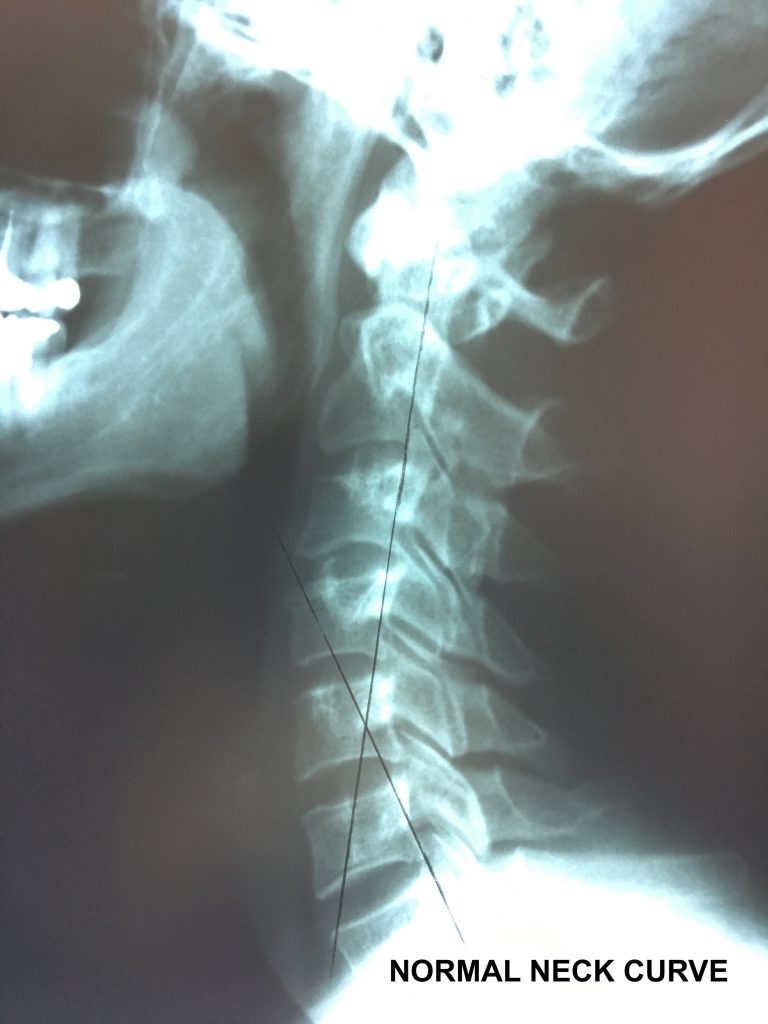

Normal vs. Abnormal Cervical XRay Chiropractic BioPhysics

Normal vs. Abnormal Cervical XRay Chiropractic BioPhysics Normal Neck X Ray Vs Whiplash so to summarize the question, yes there is a difference between whiplash and mechanical neck pain and we do treat. In the absence of clinical. Imaging plays an important role in evaluating patients with chronic neck pain. key points about whiplash. whiplash describes the manner in which a head is moved suddenly to produce a sprain in. Normal Neck X Ray Vs Whiplash.